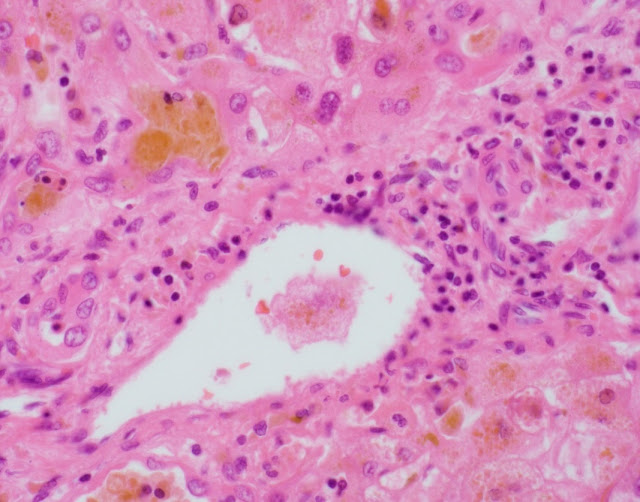

The explant showed submassive hepatocellular necrosis with marked cholestasis, and markedly dystrophic changes in bile duct epithelium in the portal tracts, but there was no ductopenia. Ductular reaction was conspicuously absent. The portal tracts showed mild chronic inflammatory infiltrate, associated with mild focal endothelialitis, and reduced number of small arterial branches. Medium-sized bile ducts showed periductal fibrosis along with dystrophic epithelial changes. Large bile ducts showed foci of intraepithelial lymphocytes, and focal reactive changes. There was central perivenulitis, with foci of lobular microabscesses. There was no foam cell arterial lesion, fibro-muscular intimal thickening, or inflammatory infiltration of muscular arteries. Trichrome stain highlighted fine perisinusoidal fibrosis, extending to portal tracts, but there is no bridging fibrosis. Reticulin showed a largely preserved architecture. A cytomegalovirus immunostain was negative.

Histologic features of chronic rejection and ischemia.

The histologic diagnostic features for CR include presence of dystrophic bile duct epithelium, bile duct loss, and foam cell obliterative arteriopathy. Some cases of late CR have also been reported to show chronic hepatitis-like changes. As has been described with acute presentations of chronic rejection, this case showed prominent inflammatory infiltrate, including endothelialitis and perivenulitis, which initially raised the histologic concern for acute rejection. The patient however remained unresponsive in spite of marked immunosuppressive therapy, and over time in the course of a few months, the inflammation reduced (reflected by the decrease in liver enzymes) whereas the bile duct dystrophy became more conspicuous, characteristically with no ductular reaction. With these clinical and histologic features, this was deemed as an unusual course of CR.